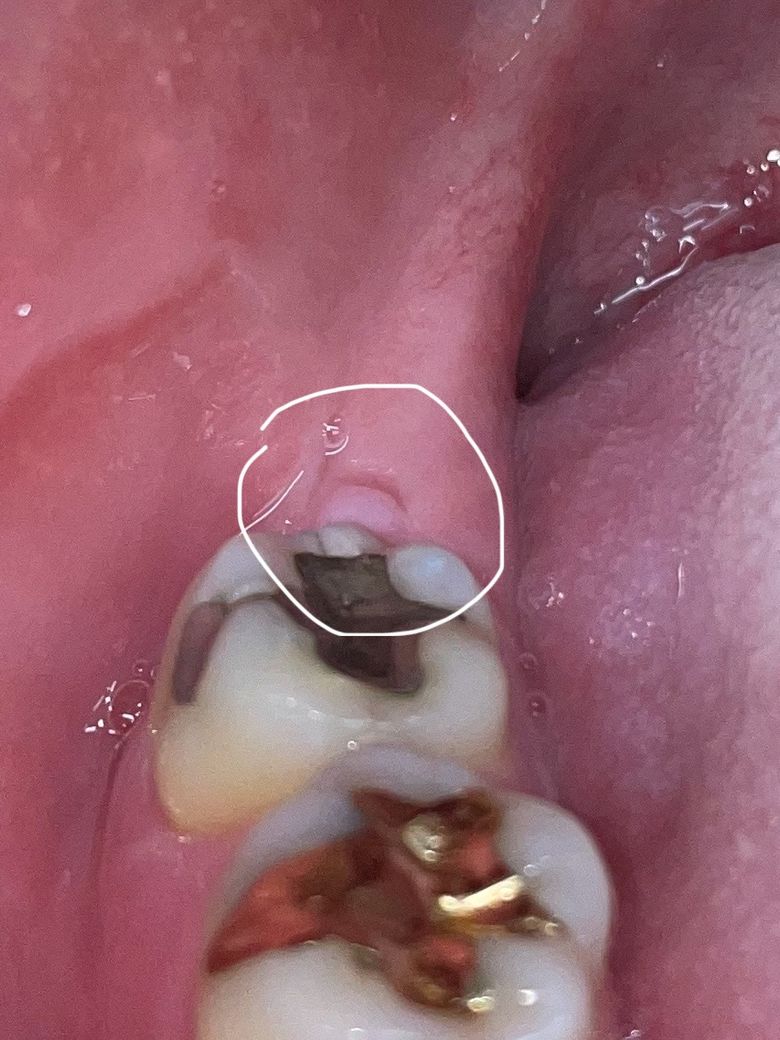

오른쪽 아래 매복 사랑니 발치 후 어금니 뒤 잇몸에 이상한 작은 혹 같은 게 생기고 통증이 있는데 크기가 점점 커지는데 이게 원인이 무엇일까요? 치과에 가니까 그냥 뭐 잇몸이 씹혀서 그렇다 괜찮다 이러는데 통증도 심하고 크기도 커지고 원인인 뭔지 원래 사랑니 발치 후 1년 지난 시점부터 생겨서 종양이나 암이나 안 좋은 질환일 수도있나요? 사진이랑 파노라마 사진 첨부합니다

저부위는 잇몸이 아물면서 생긴현상입니다. 큰 문제가 잇는건 아니니 너무 걱정하지 않으셔도 됩니다.

발치를 하고 난 다음에 해당부위가 아물면서 잇몸에 특정형태가 남아있을수 있습니다. 감염이 되지 않은것이라면 크게 문제가 되지 않기때문에 해당부위를 자극하지 않는것이 좋습니다.

사진상 크게 문제가 되어 보이는 부분이 있지는 않으나, 만약 해당부위가 더 커지고 통증이 심해지는 경우에는 절개하여 제거가 필요로 될수 있기에 치과 진료를 받길 권합니다.

단순 염증에 의한 붓기로 보이지만 사진만으로 진단을 할 수는 없으니 치과로 가보시는 게 좋겠습니다.

잇몸이 자라면서 해당부위 과증식된 것이 아닐까 싶습니다 특별히 엑스레이상으로는 문제가 없어보입니다